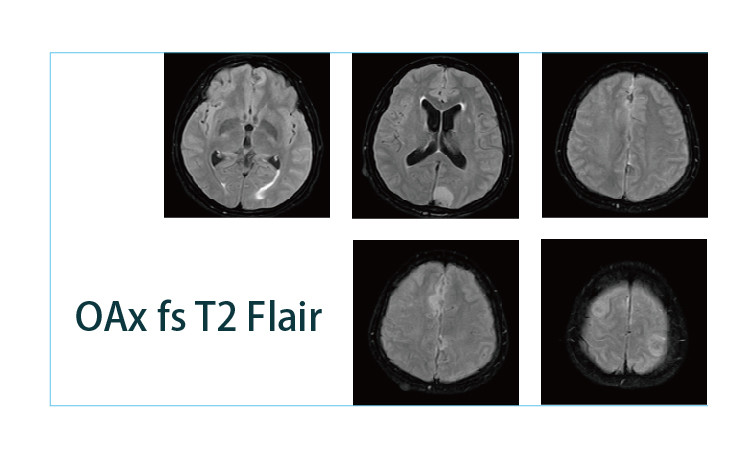

【朗润影像档案】20190412磁共振影像病例结果讨论